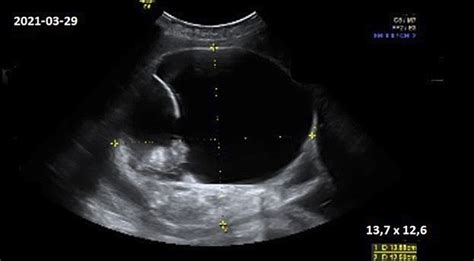

Vaizdiniai tyrimai:

- Ultragarsas (USG): Tai yra pirmo pasirinkimo tyrimas. Jis gali parodyti padidėjusią kiaušidę, cistas, skysčio kaupimąsi dubenyje ir svarbiausia - sumažėjusį ar visiškai neegzistuojantį kraujo tekėjimą kiaušidėje (Doppler tyrimas). (Cicchiello et al., 2011; Moro et al., 2020). Tačiau svarbu suprasti, kad normalūs Dopplerio radiniai nereiškia, jog torsijos nėra, ypač ankstyvose stadijose ar esant intermituojančiai (pertrūkiančiai) torsijai.